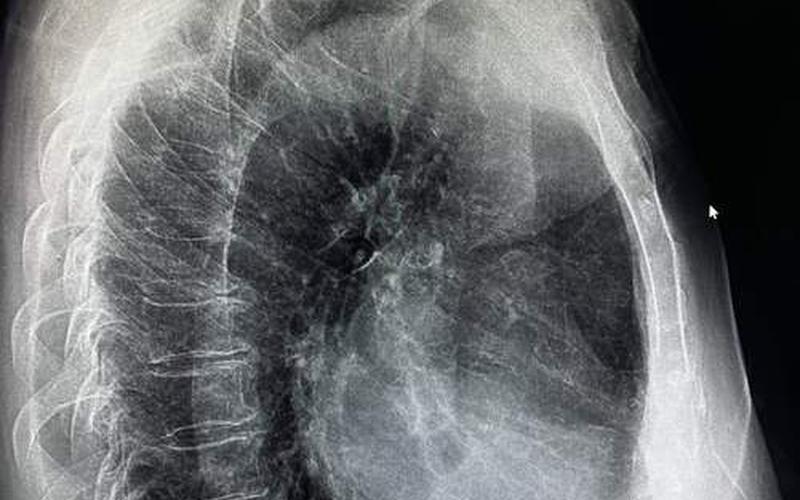

以下是一些胸片曝光大全图片,供读者参考。这些图片可以帮助读者了解胸片的成像效果,同时也可以让读者更好地理解胸片检查的过程。

(插入多张胸片曝光大全图片)